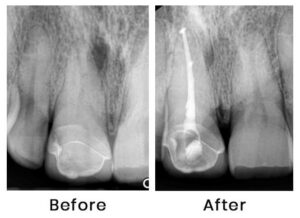

Root canal treatment means cleaning the inside of the tooth. The need to clean the inside of a tooth may emerge from inflamed or dead pulp tissue inside the tooth.